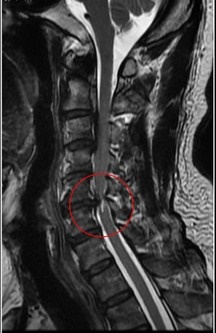

黃先生的頸椎第二節到第六節都有後縱韌帶骨化,其中第五、六節最為嚴重,脊髓已被壓得非常狹窄,核磁共振更可見明顯脊髓空洞,洪祥益主任說,這代表神經已受損,必須盡快手術,若再拖延,一旦跌倒、車禍或頸部突然甩動,都可能造成急性脊髓傷害,增加癱瘓風險。

左、中圖:黃先生的頸椎第二節到第六節都有後縱韌帶骨化,其中第五、六節最為嚴重,脊髓已被壓得非常狹窄,核磁共振更可見明顯脊髓空洞。